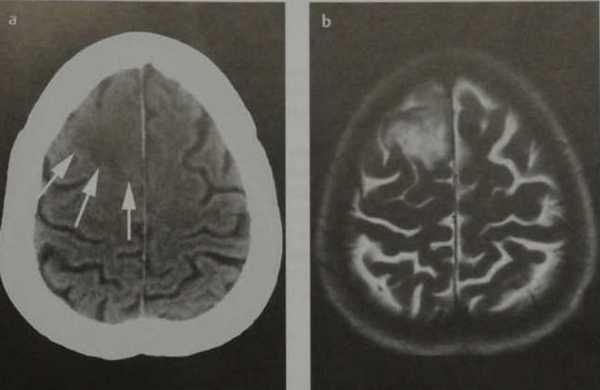

(а) МРТ, Т2-ВИ, аксиальный срез: у девушки 19 лет в лобной доле определяется гетерогенно гиперинтенсивное образование с умеренным перифокальным отеком.

(б) МРТ, постконтрастное Т1-ВИ, аксиальный срез: у той же пациентки определяется контрастирование центральной части и кистозного компонента опухоли.

Пилоцитарные астроцитомы наиболее часто локализуются в задней черепной ямке (60%) и зрительном нерве/хиазме (25-30%).

В супратенториальных отделах головного мозга пилоцитарная астроцитома (ПА) наиболее часто прилежит к III желудочку. Пилоцитарная астроцитома (ПА), локализующиеся в больших полушариях, встречаются редко.

Наличие кистозного и солидного компонентов являются типичным признаком подобных опухолей I степени злокачественности по классификации ВОЗ (grade I).